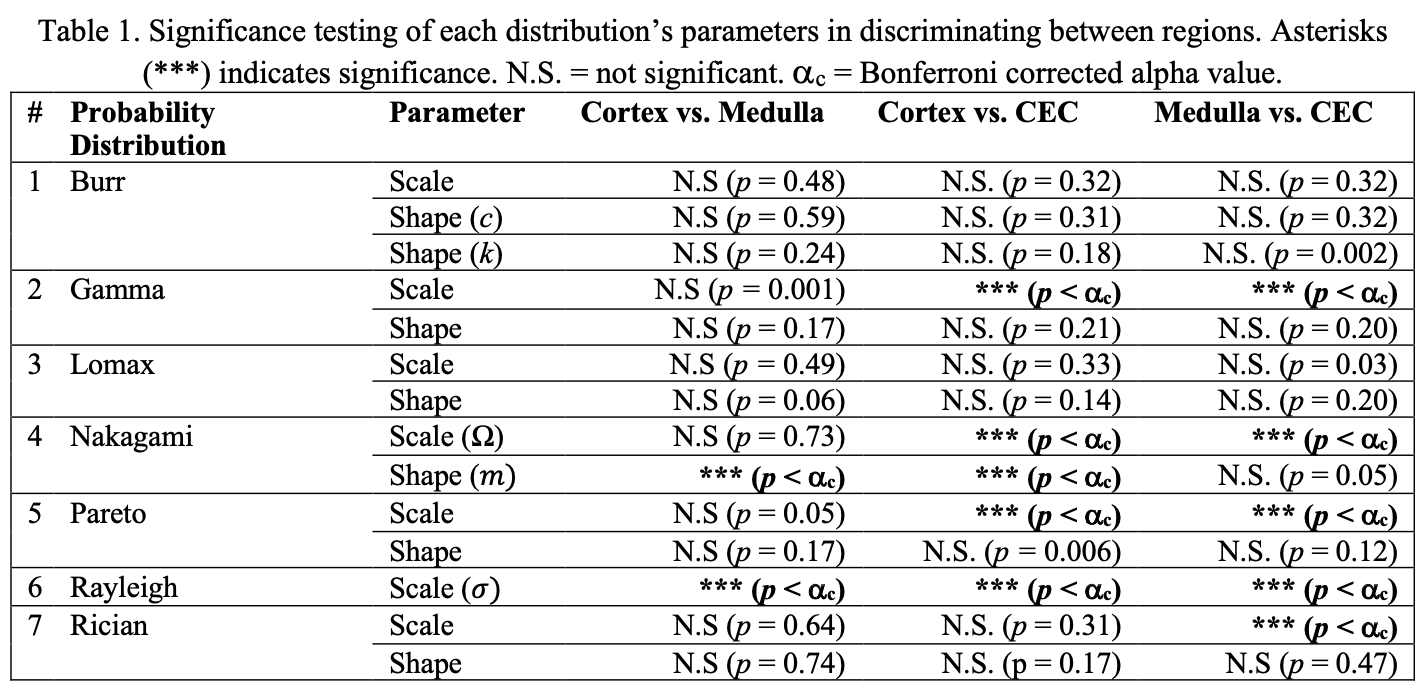

The details of the neural network’s implementation are reported by Isensee et al.. (Isensee et al., 2019) The nnU-net is trained using a separate set of 514 kidney ultrasound images, using fine-grained polygon annotations from two expert sonographers each with over 20 years of expertise. The standard 80/20 training and testing ratio is adopted. No modifications to nnU-net’s data-adaptive methodology was used resulting in a standard two-dimensional U-net being trained with an Adam optimizer, combo loss of both Dice-Sorenson Coefficient and cross-entropy, an annealed learning rate of 0.01, and 500 epochs. The computations are carried out on a single NVIDIA Tesla V100 GPU. For each extracted regional mask, the seven distributions are each fit onto the intensity values. Where possible, efficient estimators for distribution parameters were used, otherwise the maximum likelihood estimator was used. For example, in the Nakagami distribution, the inverse normalized variance estimator was used. (Kolar et al., 2004). After grouping the estimated parameters in each region across all 821 patients, the parameters can be expected to follow a normal Gaussian distribution following the Central Limit Theorem. Normality was confirmed visually. Subsequently, for each distribution, Student’s t-test was used to evaluate significance difference in the parameters between regions in a pair-wise manner. An alpha value of 0.05 was used for significance. However, given that a total of 42 comparisons on the same data were being performed, the likelihood of family-wise Type I error was high (88%). Bonferroni correction was used to adjust for this, providing a corrected alpha value of 0.0012.(Bland and Altman, 1995)

Table 1 summarizes the parameters and if they were significantly different between regions. Only two distributions, Nakagami and Rayleigh, had parameters that achieved significant differences in all three regions. These two distributions were the only ones used for subsequent KL divergence and goodness of fit analysis. Table 2 summarizes the divergence values.

Given the higher divergence values, the Nakagami distribution captures the distinctiveness of each region in a compelling manner. In comparing the cortex and medulla for example, two regions which are visually close together in echogenicity and difficult to segment, the Nakagami distribution has higher divergences compared to the Rayleigh distribution. Table 3 summarizes the goodness of fit for these distributions.

We observe low fitting error in both distributions, with no significant differences in the sum of squares error for either one. While both Rayleigh and Nakagami distributions have excellent model fitting and divergence values, the Nakagami can be used in a more general manner than the Rayleigh. The Nakagami shape parameter, m, can be used to determined pre-Rayleigh, Rayleigh, and post-Rayleigh scattering conditions. We select this distribution for stratification.

In this study, we investigated seven different probability distributions for their ability to characterize three regions of the kidney in ultrasound images of adult kidney transplant recipients. Despite the nuanced relationships between several of the distributions, we found only two distributions (Rayleigh and Nakagami) had parameters that significantly differed between the kidney’s regions. Of these two, the Nakagami may be preferred due to its generality, efficiency, and fit. The Nakagami shape parameter, , can be used to define pre-Rayleigh, Rayleigh, and post-Rayleigh scattering conditions.Shankar (2000). This enables the Nakagami distribution to characterize a wider variety of conditions than the Rayleigh alone, which relies on fully developed speckle. The efficient estimators from (Kolar et al., 2004) also make the parameters straightforward to compute. Given this however, it warrants to investigate further statistical distributions such as the generalized K or homodyned-K models. While they require intensive analytics to estimate the parameterization, the parameters are linked to signal coherency and may have specific physical meanings not captured by the Nakagami. It may also be possible to learn a distribution through machine learning techniques, rather than rely on symbolic modelling.